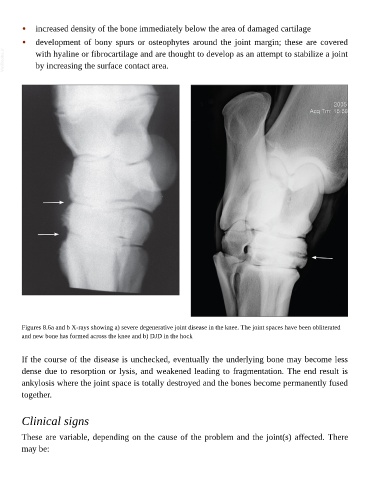

Figures 8.6a and b X-rays showing a) severe degenerative joint disease in the knee. The joint spaces have been obliterated

and new bone has formed across the knee and b) DJD in the hock